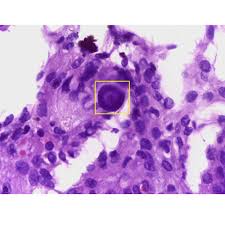

Mesothelioma Histology Usmle : Asbestosis And Silicosis Causes And Treatments Medical Library / Mesothelioma histology is the study of the function and structure of anatomy, including tissues and cells.. Histology isn't historically the most high yield topic on the boards, but the questions that have a histology image included can be easy points if you take a step back, don't freak out. Histology also helps avoid misdiagnosis of mesothelioma. Generally mesothelioma is an aggressive and deadly form of cancer. Mesothelioma videos, flashcards, high yield notes, & practice questions. Malignant mesothelioma treatment may include surgery, radiation therapy, and chemotherapy.

Quickly memorize the terms, phrases and much more. Mesothelioma histology includes the study of cancerous mesothelioma cells. Our mesothelioma course covers all essentials: Histology, or histopathology, is essential to define cancer cells at their most basic level. The histology of mesothelioma can provide insight to those who have been or have loved ones diagnosed with this cancer.

Malignant mesothelioma treatment may include surgery, radiation therapy, and chemotherapy. Malignant pleural mesothelioma is an aggressive cancer with poor prognosis, linked to vascular endothelial growth factor is a key mitogen for malignant pleural mesothelioma cells. Many mesothelioma specialists favor histology over any other form of diagnosis, including cytology, because it's the most. Mesothelioma is a type of cancer that develops from the thin layer of tissue that covers many of the internal organs (known as the mesothelium). Like any other cancer issues. Quickly memorize the terms, phrases and much more. Peritoneal mesothelioma and ovarian cancer, for example. Cell biology, histology, general pathology at cram.com. Mesothelioma is difficult to diagnose by examining the macrostructure of the tumor. Histology also helps avoid misdiagnosis of mesothelioma. Tumor markers, from first aid for the usmle step 1 learn with flashcards, games and more — for free. Mesothelioma is a rare form of cancer in which malignant (cancerous) cells are found in the mesothelium most people who develop mesothelioma have worked on jobs where they inhaled asbestos particles. Other risk factors for mesothelioma include exposure to thorotrast and repeated mesothelial irritation.

Histology also helps prevent mesothelioma misdiagnosis. Mesothelioma's histology reveals epithelial and sarcomatoid cell types. Germline bap1 mutation has been associated with early onset and less. Pathologists examine macrostructures, but also microscopic structures like cells. Histology isn't historically the most high yield topic on the boards, but the questions that have a histology image included can be easy points if you take a step back, don't freak out.

Usmle Step 1 High Yield Free Download Borrow And Streaming Internet Archive from archive.org Mesothelioma is a malignancy involving mesothelial cells that line the body cavities, including the pleura, peritoneum, pericardium, and testis. Many mesothelioma specialists favor histology over any other form of diagnosis, including cytology, because it's the most. Analyzing the cell type helps doctors tell the difference. Generally mesothelioma is an aggressive and deadly form of cancer. Quickly memorize the terms, phrases and much more. An important tool used in the definitive diagnosis of disease is histology, the microscopic examination of cellular anatomy. Histology also helps avoid misdiagnosis of mesothelioma. Cell biology, histology, general pathology at cram.com.

Mesothelioma's histology reveals epithelial and sarcomatoid cell types. Mesothelioma treatments are available, but for many people with mesothelioma, a cure isn't possible. Mesothelioma most often develops in the lining of the lungs and pleural cavity, and is well known for its association with. Histology, or histopathology, is essential to define cancer cells at their most basic level. Histology also helps prevent mesothelioma misdiagnosis. Cram.com makes it easy to get the grade you want! Histology also helps avoid misdiagnosis of mesothelioma. Mesothelioma histology includes the study of cancerous mesothelioma cells. Histology isn't historically the most high yield topic on the boards, but the questions that have a histology image included can be easy points if you take a step back, don't freak out. Other risk factors for mesothelioma include exposure to thorotrast and repeated mesothelial irritation. The histology of mesothelioma can provide insight to those who have been or have loved ones diagnosed with this cancer. Learn more from shrader & associates l.l.p. Like any other cancer issues.

Ct And Mr Imaging Of Cardiac Tumors Ppt Video Online Download from slideplayer.com Analyzing the cell type helps doctors tell the difference. Study flashcards on usmle step 1: Mesothelioma is a malignancy involving mesothelial cells that line the body cavities, including the pleura, peritoneum, pericardium, and testis. Mesothelioma videos, flashcards, high yield notes, & practice questions. Malignant mesothelioma treatment may include surgery, radiation therapy, and chemotherapy. Like any other cancer issues. Mesothelioma is a rare form of cancer in which malignant (cancerous) cells are found in the mesothelium most people who develop mesothelioma have worked on jobs where they inhaled asbestos particles. This disease's three main cell a pathologist examines tissue samples under a microscope and uses histology techniques to diagnose.

Mesothelioma videos, flashcards, high yield notes, & practice questions. Germline bap1 mutation has been associated with early onset and less. Mesothelioma histology is the study of mesothelioma cell types. Cell biology, histology, general pathology at cram.com. Many mesothelioma specialists favor histology over any other form of diagnosis, including cytology, because it's the most. Analyzing the cell type helps doctors tell the difference. Mesothelioma is a rare form of cancer in which malignant (cancerous) cells are found in the mesothelium most people who develop mesothelioma have worked on jobs where they inhaled asbestos particles. Peritoneal mesothelioma and ovarian cancer, for example. Other risk factors for mesothelioma include exposure to thorotrast and repeated mesothelial irritation. For example, peritoneal mesothelioma and ovarian cancer can be difficult to differentiate. Pathologists examine macrostructures, but also microscopic structures like cells. Mesothelioma is a type of cancer that develops from the thin layer of tissue that covers many of the internal organs (known as the mesothelium). Histological analysis of malignant tissue is an invaluable tool in diagnosing a patient's mesothelioma, as well as monitoring.